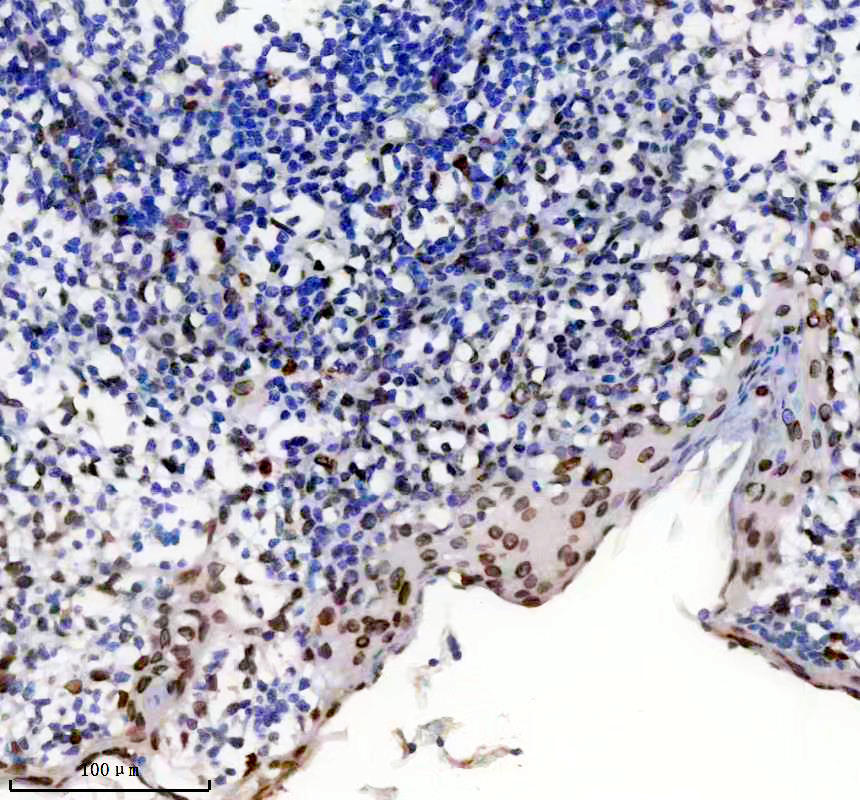

IHC analysis of Lamin A/C using anti-Lamin A/C antibody (BM4105).

Lamin A/C was detected in a paraffin-embedded section of human tonsil tissue. The tissue section was incubated with rabbit anti-Lamin A/C Antibody (BM4105) at a dilution of 1:200 and developed using HRP Conjugated Rabbit IgG Super Vision Assay Kit (Catalog # SV0002) with DAB (Catalog # AR1027) as the chromogen.